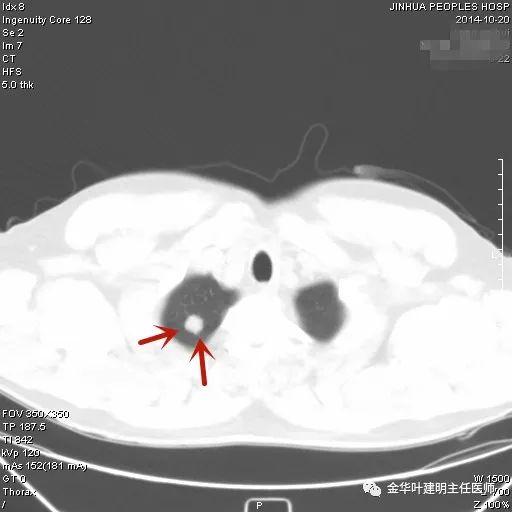

上图示结核。我们发现其有明显的卫星灶,如绿色箭头所示,主病灶处也是周边有模糊区域,病灶整体密度较为均匀(肿瘤容易生长不均致密度欠均匀,显杂乱)。